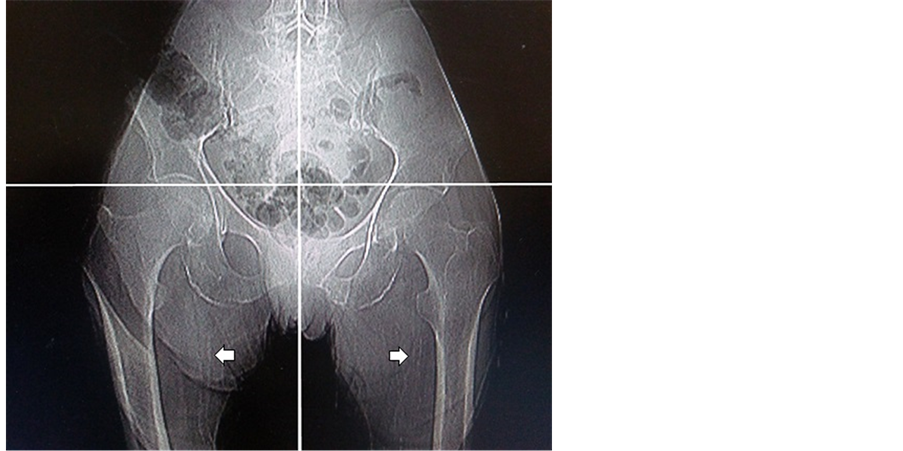

4.6. Distribution of Vascular Calcification

The radiographic films in our study showed that there were 80% calcifications of iliac arteries, 15% calcifications of femoral arteries and 5% vascular calcification in radiograph of the hands. Examples of vascular calcification of the studied patients were presented in Figure 1 and Figure 2.

Figure 2. Pelvic radiography shows calcification of the femoral arteries. Simple vascular calcification score of the pelvis example is 2.